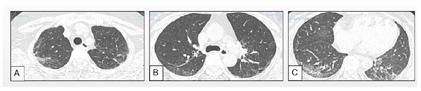

患者从2019年8月9日应用哌拉西林他唑巴坦钠4.5 g每8小时1次,共10 d,注射人免疫球蛋白20 g/d,共5 d,同时应用"贝前列腺素片40 µg每日3次","泼尼松30 mg每日1次(逐渐减量)","吡非尼酮0.3 g每日1次",应用奥美拉唑、钙片、阿法骨化醇等药物对症治疗;2019年8月24日开始每月静脉注射环磷酰胺1.0 g用6次,每3个月1.0 g用3次,累计9 g;后因为患者输注环磷酰胺后间质性肺炎较前加重(图2A~C),由于患者胃肠道副作用、月经周期紊乱、皮肤硬化缓解不明显、输液困难等原因,于2020年11月开始停用环磷酰胺输注,调整为口服托法替布5 mg每日2次,余治疗同前。

2021年9月复查,患者mRSS评分为13,血沉10.2 mm/h,C反应蛋白4.31 mg/dl,白细胞8.78×109/L,6MWD(6分钟步行试验) 512 m。患者间质性肺炎较前好转,肺纤维化评分Sverzellati视觉评分8分(2019年8月,2020年2月,2020年6月,2020年11月,2021年9月:23分→15分→8分→13分→8分)。